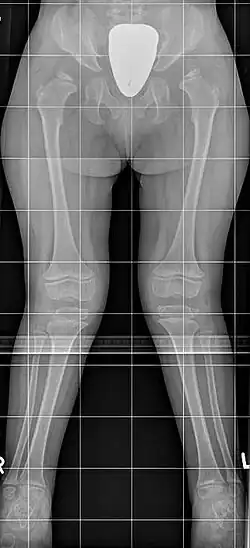

![]() Синдром Моркио: на рентгенограмме с двух сторон отмечается укорочение шейки бедра, в результате чего уменьшается поперечник таза; крылья подвздошных костей неправильной формы; характерна вальгусная деформация нижних конечностей | |

Мукополисахаридоз IV типа или синдром Моркио — наследственное заболевание из группы лизосомных болезней накопления, впервые описано L. Morquio в 1929 году[1]. Клинические проявления характеризуются значительными деформациями скелета, особенно грудной клетки. В отличие от других типов мукополисахаридозов, IV тип характеризуется отсутствием снижения интеллекта, помутнения роговицы, гепатоспленомегалии и гротескных черт лица.